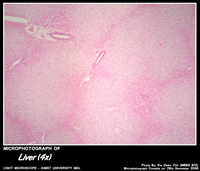

LIVER

Histology of Liver

• Made up of hexagonal areas – hepatic lobules.

• Each separated – connective tissue septa.

• Each lobule has cords of liver cells separated by sinusoids.

• Along the periphery of each lobule there an area filled with connective tissue.

• This area is called the portal canals.

• Portal canals has

• 1. branch of portal vein

• 2. branch of hepatic artery

• 3. interlobular bile duct

• knowns as PORTAL TRIAD

• Blood from the portal vein, hepatic artery enter the sinusoids at the periphery of the lobule.

• The blood flows towards the centre and open into a vein in the middle called central vein .

• Central veins drains into the hepatic vein – IVC